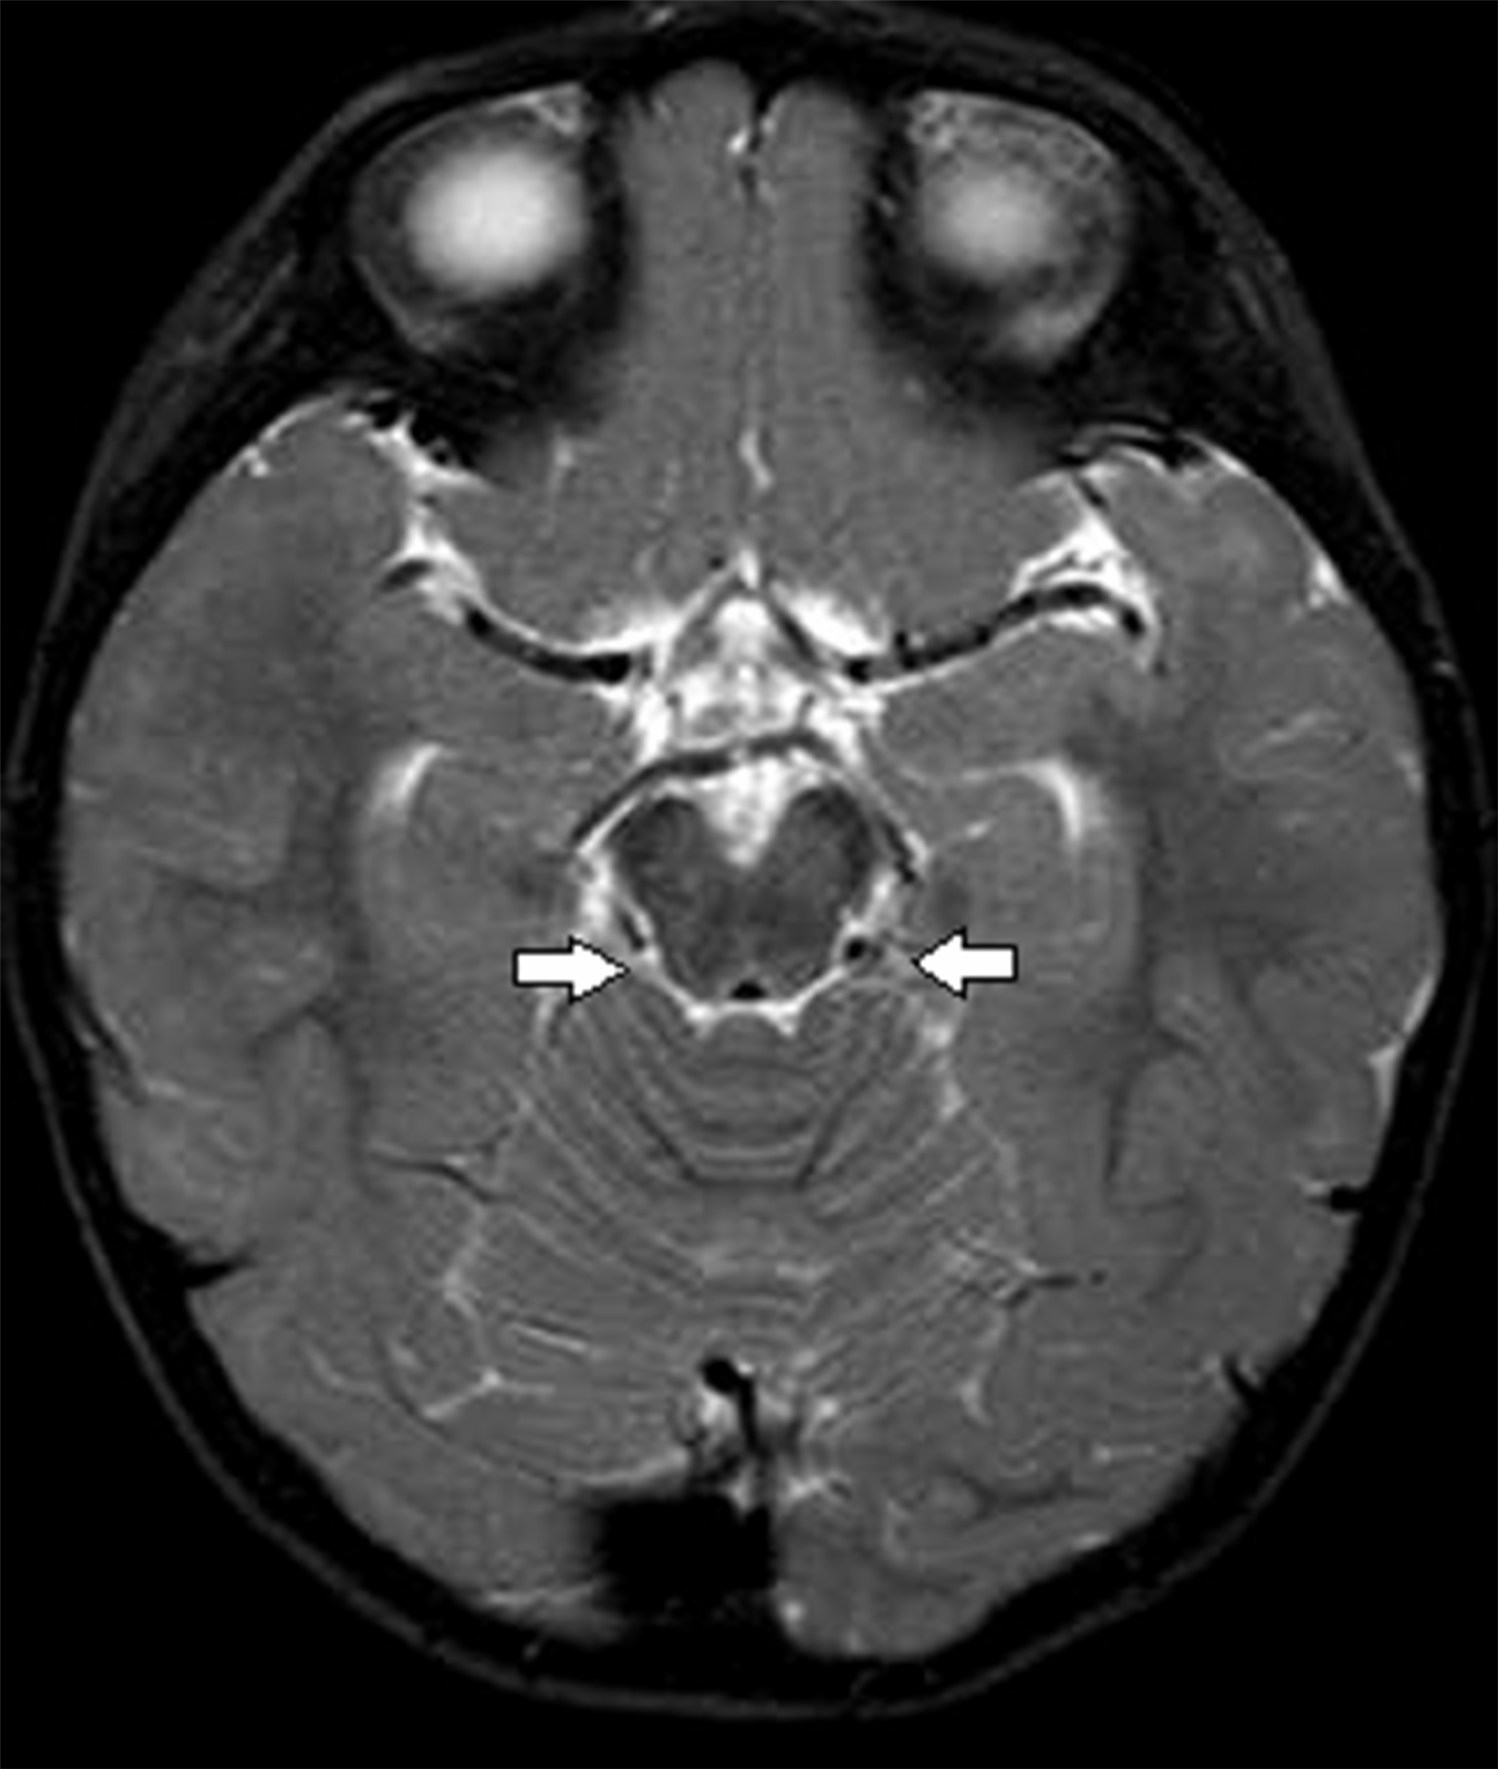

Figure 4 of Yang, Mol Vis 2013; 19:986-994.

Figure 4. Magnetic resonance imaging of the brain of proband III:2. The thin linear structure coursing obliquely from the left pontomedullary region in the left pontine cistern suggests the left abducens nerve, which was absent in the right side.